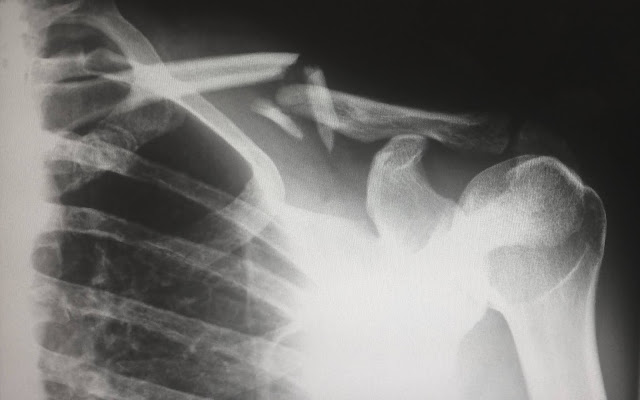

6.2 Fracturas más frecuentes: definición de fracturas, tipos, signos y síntomas, métodos diagnósticos, inmovilizaciones